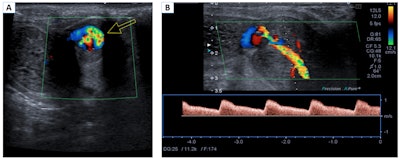

Nonischemic or high-flow priapism. Color Doppler in the transverse plane (A) and spectral Doppler in the longitudinal plane (B). Turbulent flow of the left cavernous artery is observed (arrow). The lesion shows a low resistance pattern, with increased systolic and diastolic velocities. These findings are related to a penile pseudoaneurysm.

Priapism occurs when a pathological penile erection persists for four hours or more and is not related to sexual stimulation. It is classified as low-flow priapism (ischemic or veno-occlusive) and high-flow priapism (not ischemic or arterial). Imaging tests are not usually necessary, and cavernous blood gas levels can help to confirm the diagnosis, the Madrid team stated.